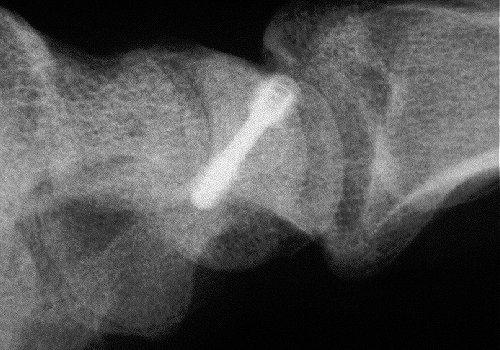

Xray before

and two months postop: